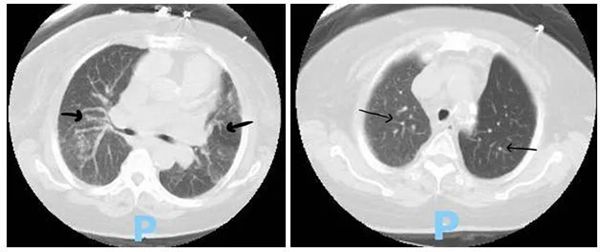

X线检查显示双侧肺部阴影,胸部CT(图1)检查提示间质性肺疾病伴有间质增厚,支气管扩张并形成蜂窝状。

(图1 胸部CT检查

)

RA-ILD的症状可从无症状到快速致命性急性间质性肺炎。通常情况下,症状会隐匿地发展,可导致劳累性呼吸困难以及无痰干咳。RA-ILD以活动时呼吸困难为主要症状,呈渐进性加重特点,体征早期双肺底可闻及吸气末细小的干性爆裂音或VeIcro啰音,晚期还可出现杵状指,肺动脉高压和肺心病体征,高分辨率CT(HRCT)检查以弥漫性结节影、磨玻璃样变、肺泡实变、小叶间隔增厚、胸膜下线、网格影伴囊腔形成或蜂窝状改变为主要特点,常伴牵拉性支气管扩张或肺结核